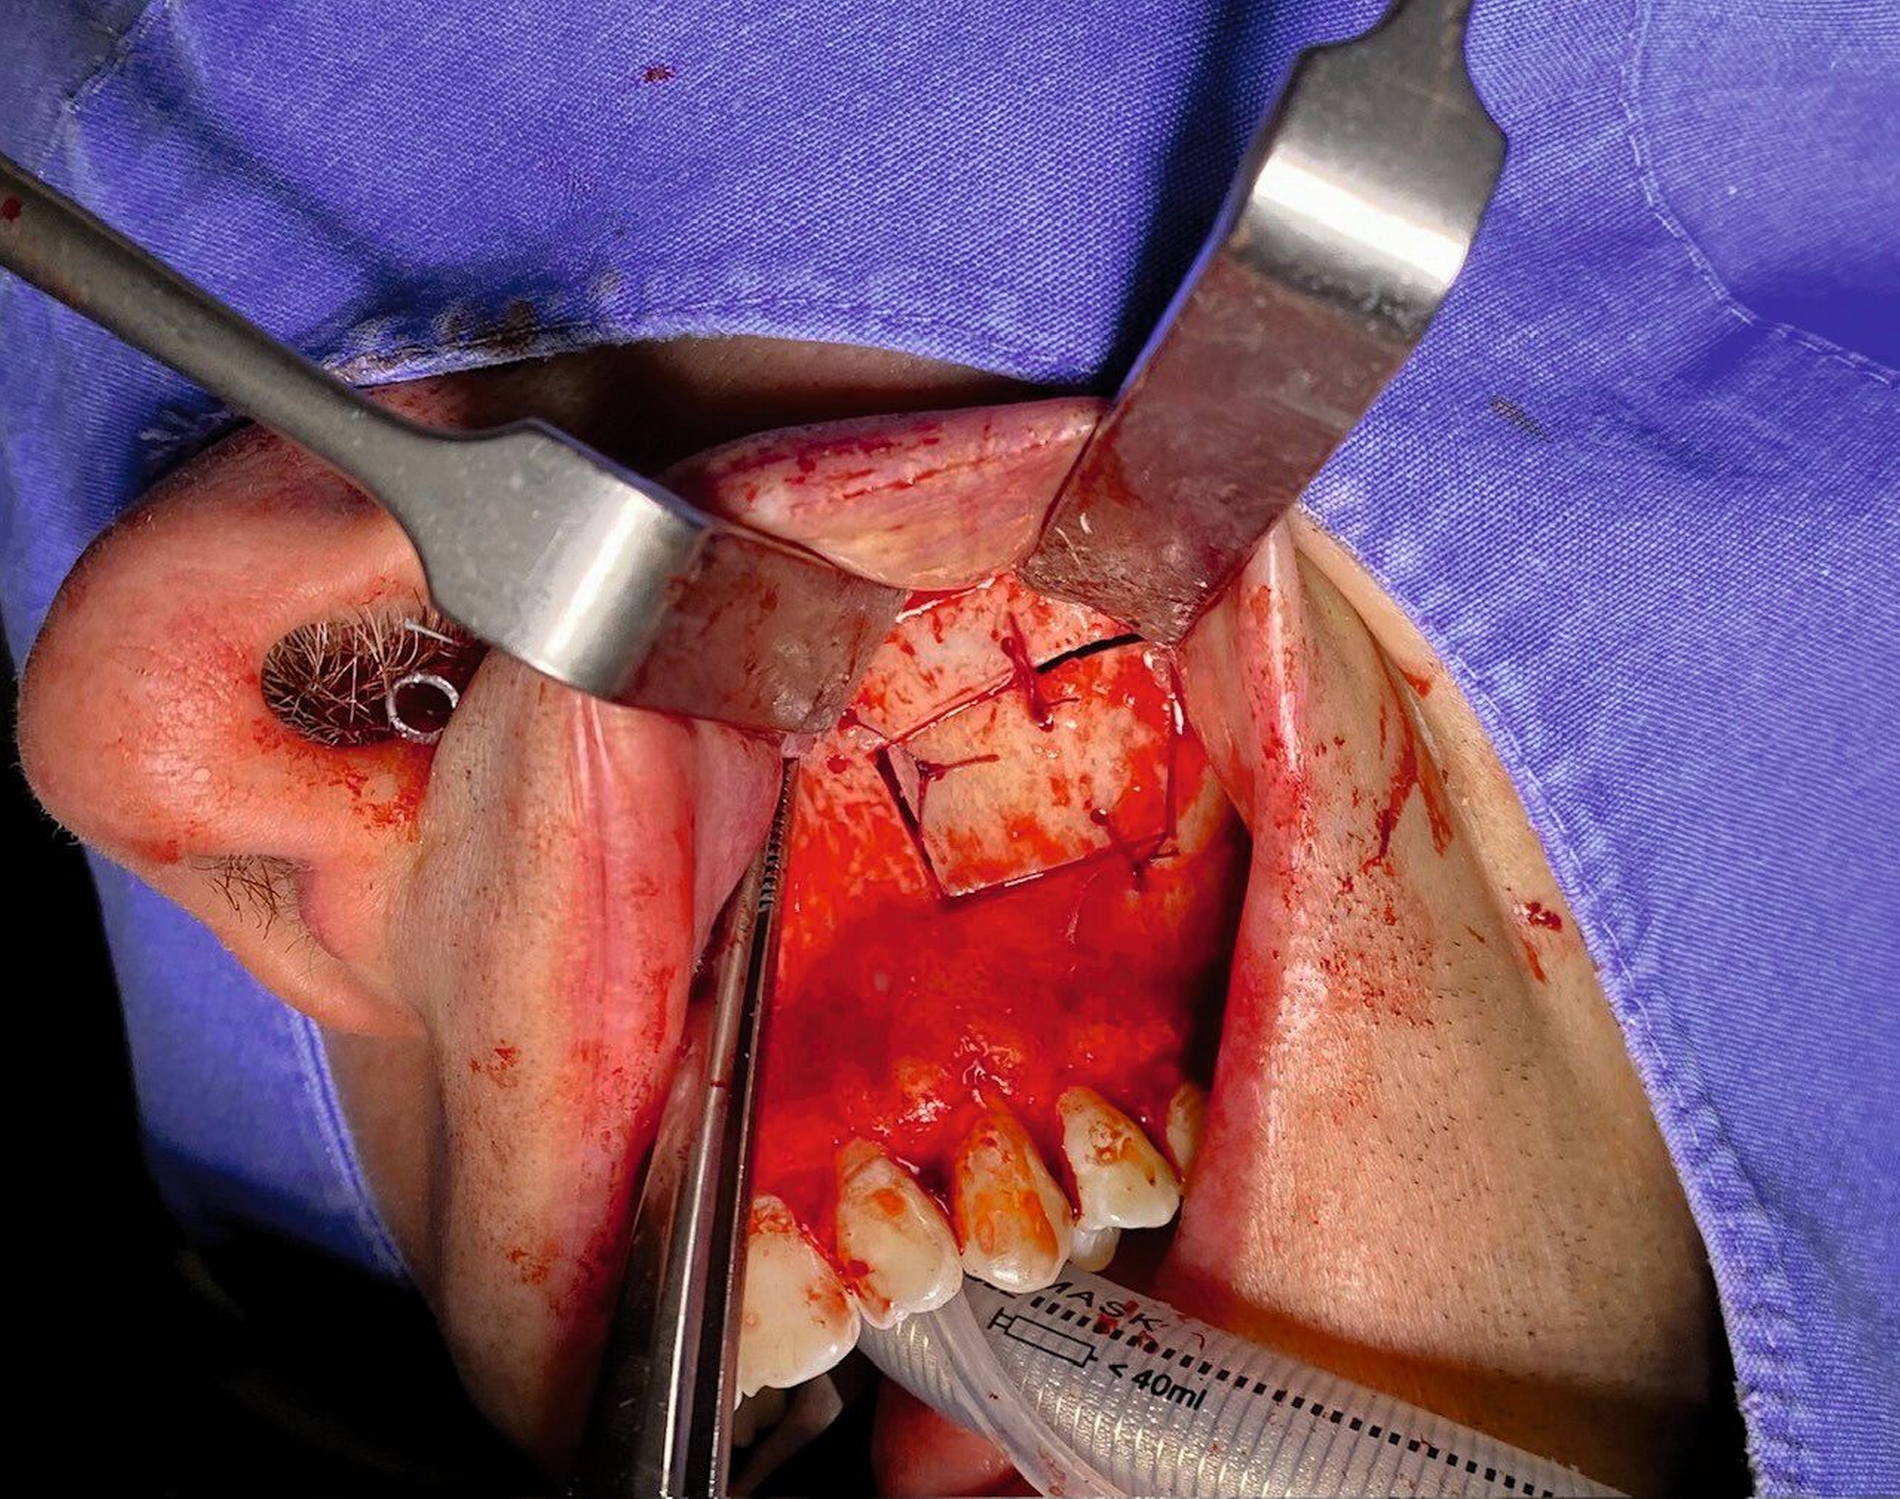

Die Therapie erfolgte in ambulanter Vollnarkose mittels Lindorf-Deckel-Technik. Nach marginaler Schnittführung und Darstellung der Kieferhöhlenvorderwand wurde mittels Piezosurgery ein knöcherner Deckel präpariert und der Sinus eröffnet (Abbildung 3). Es zeigten sich eine große Menge bröckeliges, schwarz verfärbtes Material sowie eine entzündlich veränderte Schleimhaut (Abbildung 4).